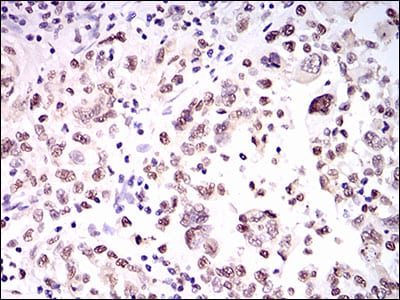

- Immunohistochemical analysis of paraffin-embedded human colon cancer tissues using HNRNPU mouse mAb with DAB staining.

- Immunohistochemical analysis of paraffin-embedded human endometrial cancer tissues using HNRNPU mouse mAb with DAB staining.